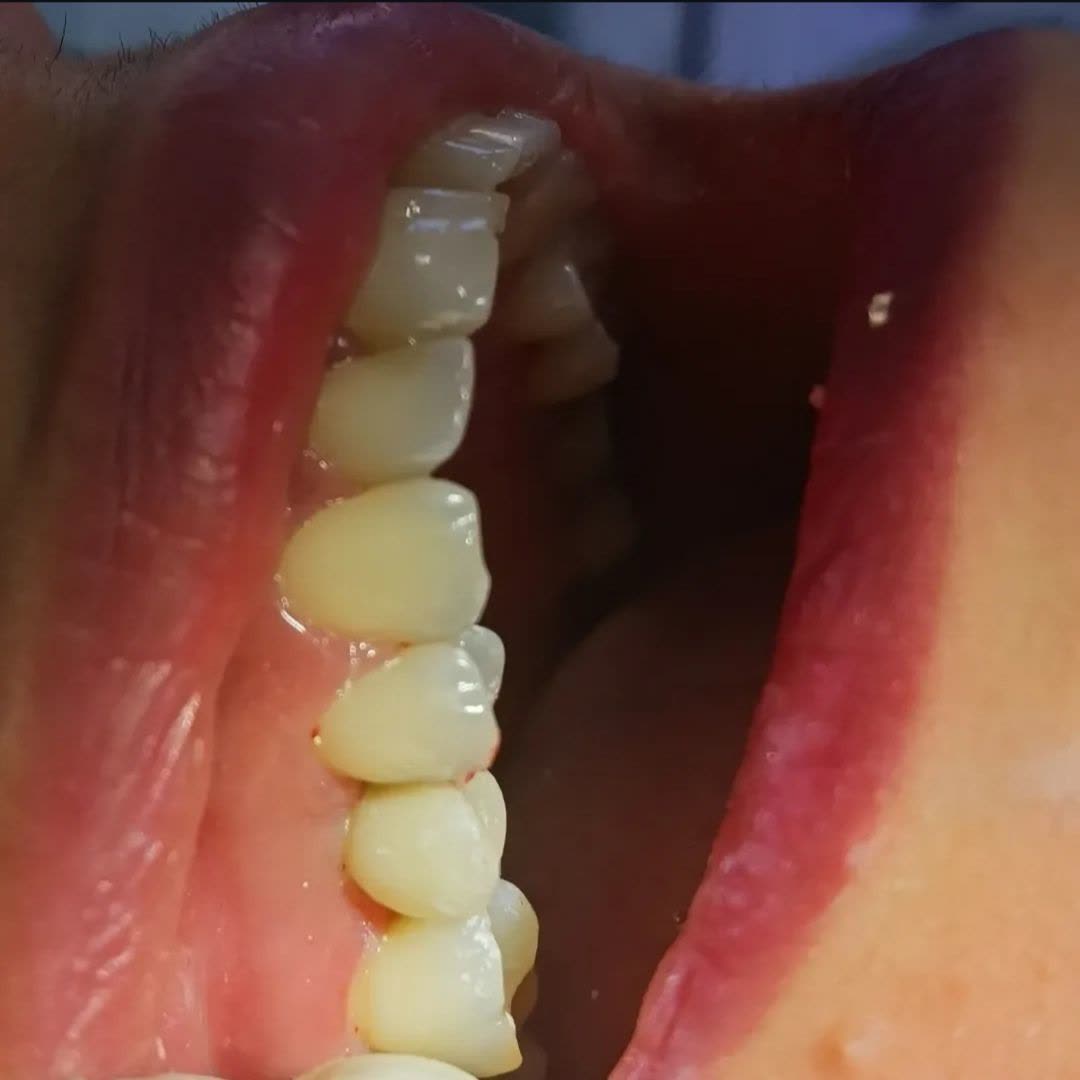

دکتر ناهید علیان نجف آبادی دارای دکترای حرفه‌ای دندانپزشکی است که در شهر نجف آباد فعالیت می‌کند. ایشان در حوزه درمان بیماری‌ها و مشکلات دهان و دندان تخصص داشته و از پزشکان برجسته در زمینه ایمپلنت و خدمات زیبایی دندان به شمار می‌روند.

• کامپوزیت ونیر و لمینت سرامیکی

• ترمیم دندان با روش بایومیمتیک

• ارائه خدمات دندانپزشکی زیبایی مانند لمینت و کامپوزیت